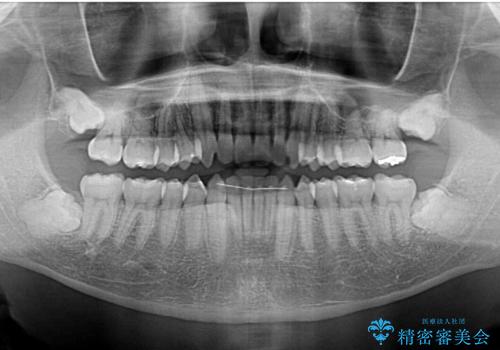

- 上下前歯のデコボコと深い咬み合わせを気にして来院された患者様です。

インビザラインによる上下歯列の拡大と、IPR(歯と歯の間を削る)にるスペースの獲得により、前歯のデコボコとディープバイトを改善することとしました。

もう少し下の前歯を整えたかったのですが、患者様の治療を早く終了させたいという希望により、細かい叢生を残しての終了となりました。